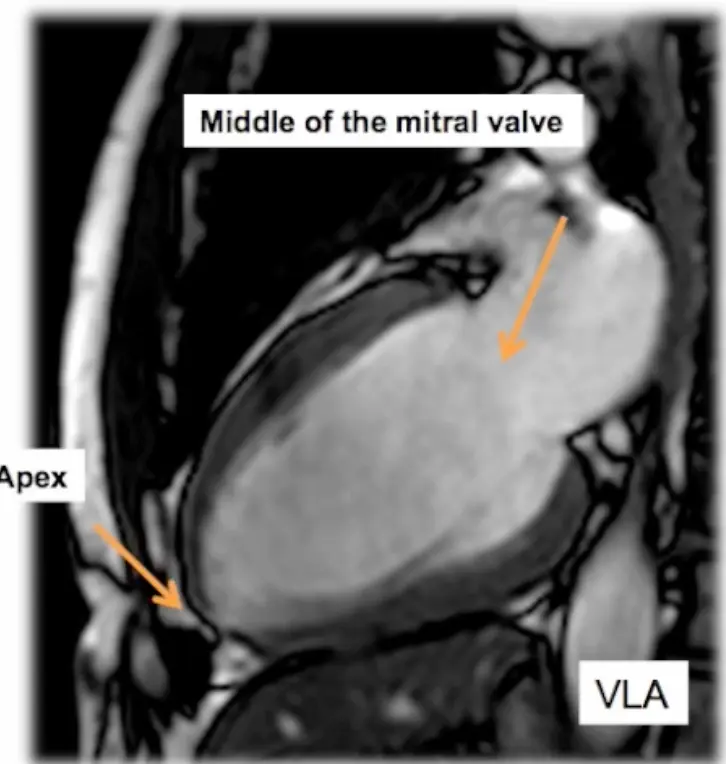

- Step 1. Scouts and planning views (VLA, HLA)

- We begin with the transverse LAX view and position the line marker dissecting the apex and the middle of the mitral valve (where the two leaflets meet) → results in a vertical LAX (VLA) view, aka pseudo 2 chamber (p2CH) view

- Next we slice the resulting VLA view: again, we cut across the apex and the middle of the mitral valve (where the two leaflets meet) → results in a horizontal LAX (HLA) view

- Resulting scout views include VLA and HLA views